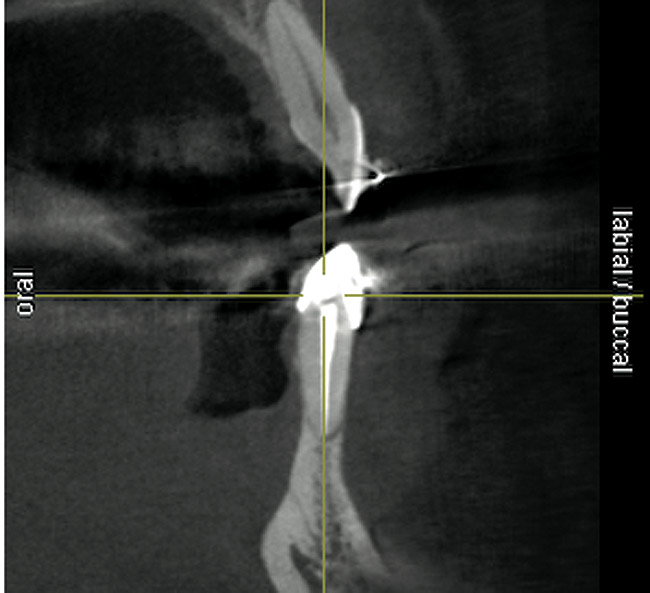

Figure 19  Scanning appliance worn by the patient for CT scan (Fig 19). Fabrication of a surgical template for flapless, computer-guided implant placement would be based on digital information obtained from the scan. Fig 20 demonstrates the cross-sectional view of the No. 8 position. Planning software demonstrated adequate 3-D volume for implant placement in this regenerated area where rhBMP-2/ACS and mesh were combined.

Figure 19

Figure 20  Scanning appliance worn by the patient for CT scan (Fig 19). Fabrication of a surgical template for flapless, computer-guided implant placement would be based on digital information obtained from the scan. Fig 20 demonstrates the cross-sectional view of the No. 8 position. Planning software demonstrated adequate 3-D volume for implant placement in this regenerated area where rhBMP-2/ACS and mesh were combined

Figure 20